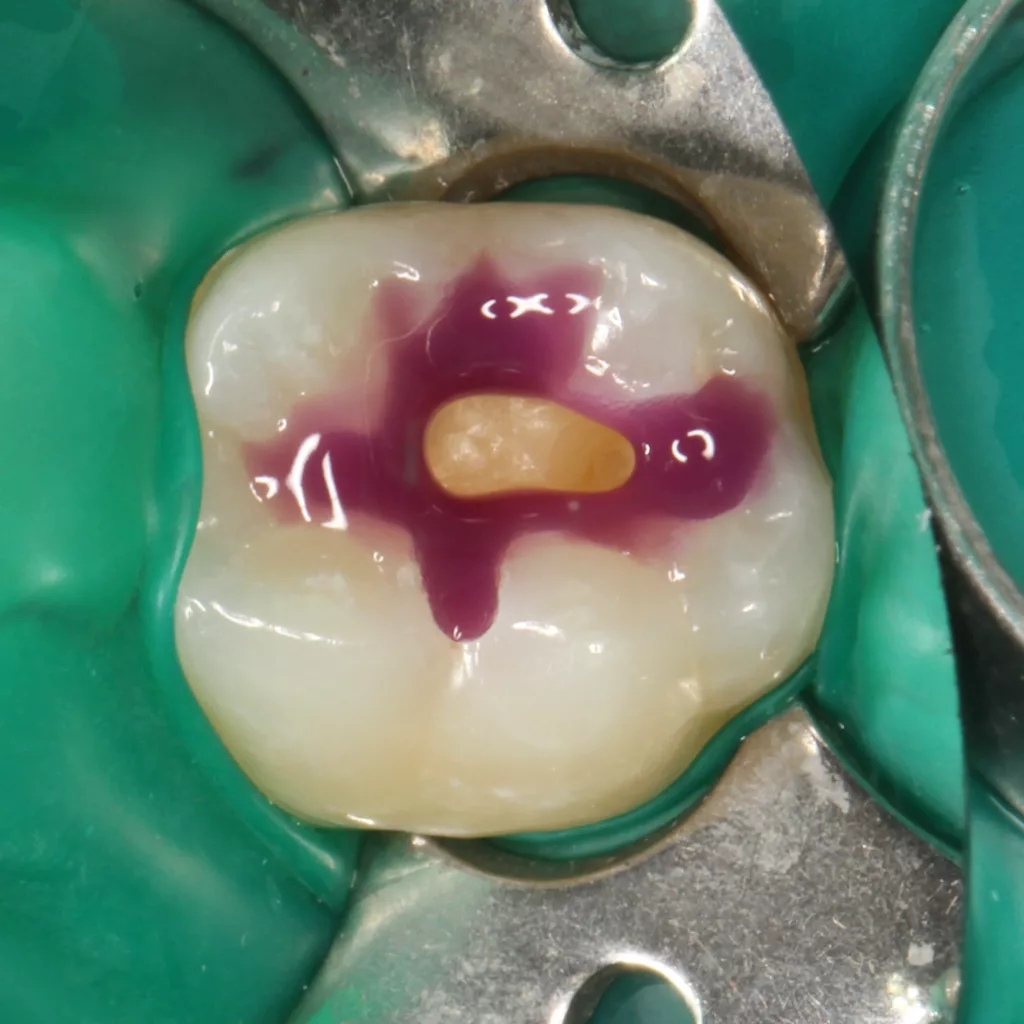

Fall 5: Versorgung einer okklusalen Kavität an einem unteren Molaren

Auch im Molarenbereich können Bulkflow-Materialien effektiv und ökonomisch eingesetzt werden, ohne Abstriche an der Ästhetik machen zu müssen, was der Fall des hier versorgten Zahnes 46 bei einer 22-jährigen Patientin zeigt. Die Abbildung 24 stellt die bereits präparierte und mit einem Einzelzahnkofferdam isolierte Kavität mit der Phosphorsäurekonditionierung der Schmelzränder (Gel Etchant, Kerr) dar. Die Entscheidung zur absoluten Trockenlegung fiel aufgrund der nicht so einfach kontrollierbaren Zunge und der vielen Schluckreflexe, was das Risiko einer ungewollten Speichelkontamination der Klebefläche unverhältnismäßig erhöhte.

Die Verwendung des Kofferdams ist generell eine sehr empfehlenswerte, aber keine zwingende Voraussetzung zur Etablierung einer suffizienten Kontaminationskontrolle [47,96]. Das bisher auch bereits verwendete Zwei-Schritt-Universaladhäsiv G2 Universal wurde hier in der selektiven Schmelzätztechnik angewendet, d.h., das Material arbeitet auf dem Dentin selbstkonditionierend (Abb. 25). Die bislang zu diesem innovativen Mehrflaschen-Universaladhäsiv publizierten Daten zeigen eine beeindruckende Performance, die den Vergleich mit sogenannten Goldstandards [98] wie einem Optibond FL nicht scheuen müssen [13,18,34,58,63,114,119,127,130]. Im nächsten Schritt wurden die einzelnen Höcker mit dem angenehm standfesten Flowable aufgebaut (Abb. 26). Die Abbildung 27 zeigt die komplett versorgte okklusale Kavität, die Abbildung 28 die Situation unmittelbar nach Ausarbeitung und Politur. Erneut beeindruckt die gute Farbadaptation.